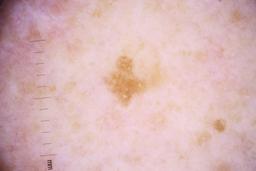

ISIC_4077341

- Challenge 2020: Training

- IP_1969685 IL_9238622

Clinical

| Field | Value |

|---|---|

| acquisition_day | 1 |

| age_approx | 50 |

| anatom_site_1 | Trunk |

| anatom_site_2 | Anterior trunk |

| concomitant_biopsy | False |

| dermoscopic_type | contact non-polarized |

| diagnosis_1 | Benign |

| diagnosis_confirm_type | serial imaging showing no change |

| family_hx_mm | False |

| image_type | dermoscopic |

| lesion_id | IL_9238622 |

| patient_id | IP_1969685 |

| personal_hx_mm | True |

| sex | male |